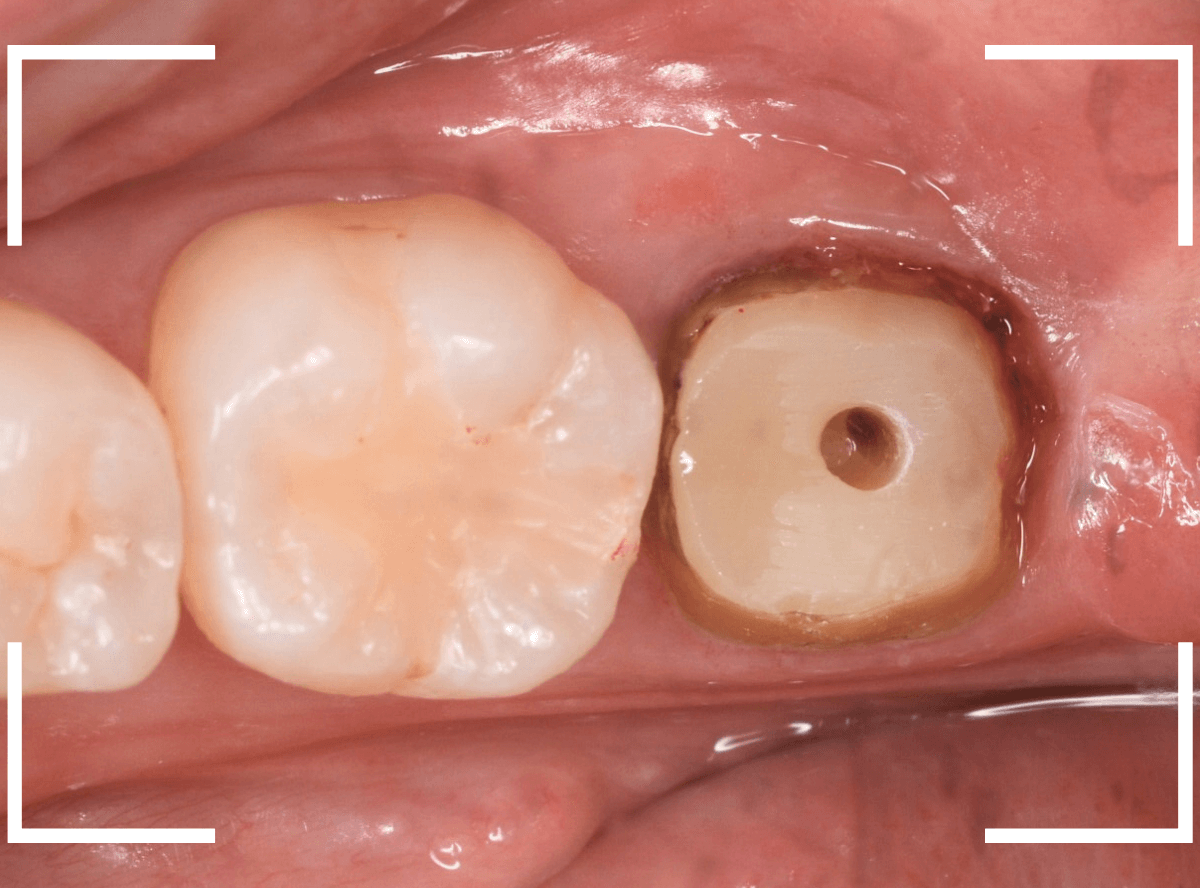

さし歯の土台の補修と、おやしらずの虫歯の処置をしたところです。

この状態で型をとります。